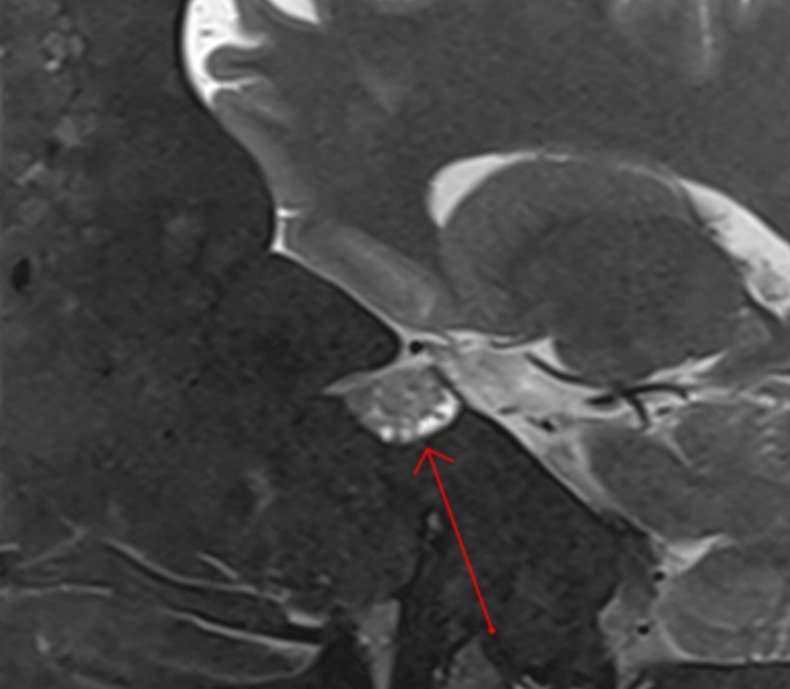

Endoscopic endonasal transsphenoidal approach of pituitary macroadenoma and optic canal stenosis in a patient with McCune-Albright syndrome.

Abstract Image